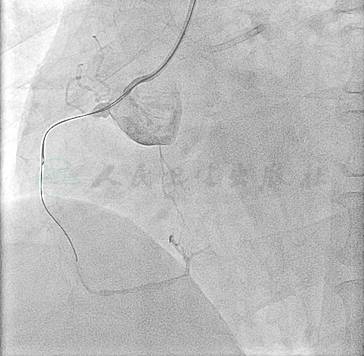

予2%利多卡因局部浸润麻醉,穿刺右侧桡动脉成功后经导丝置入6F动脉鞘。在长导引钢丝引导下,用5F TIG导管行左右冠状动脉造影,左主干未见明显狭窄,前降支近段狭窄90%伴斑块破裂征象,中远段弥漫性长病变,狭窄70%~80%,第一对角支全程狭窄40%~50%,回旋支近段管壁不规则伴扭曲,近中段完全闭塞,第一钝缘支提供侧支循环供应回旋支远端;右冠近段完全闭塞,可见少许圆锥支侧支使右冠远段显影(图1~图3)。

图3 右冠近段完全闭塞

穿刺左侧桡动脉,置入6F动脉鞘,经导丝直接送入6F EBU3.5指引导管至左冠口行对侧造影,经右侧桡动脉送6F AL0.75指引导管至右冠口造影,双侧造影提示右冠远端侧支主要来源于同侧右冠口的圆锥支(图4),因此决定行正向技术尝试。首先在1.8F Finecross微导管支撑下选择0.009〞Fielder XT导丝进入右冠近段假腔(图5),换用0.014〞Miracle 3导丝仍进入右冠中段假腔(图6),采用平行导丝技术再送另一根0.014〞Miracle 3导丝在同侧造影指导下尝试进入右冠中段真腔(图7、图8),反复调整导丝方向后成功送Miracle 3导丝至右冠后降支远端,多角度造影证实导丝远端位于真腔(图9),由于Ryujin plus 2.0mm×20mm球囊无法通过右冠闭塞处,取Ryujin plus 1.5mm×15mm球囊于闭塞处以12atm×10s扩张,经微导管交换0.014〞Runthrough导丝至右冠远端,再以Ryujin plus 2.0×20mm球囊以10atm×10s扩张(图10),复查造影示右冠恢复前向血流(图11),于右冠中段至右冠开口串联依次植入Excel 3.0mm×36mm,Excel 3.5mm×36mm西罗莫司药物支架,分别以14 atm扩张释放,并以16 atm支架球囊扩张塑型(图12、图13),复查造影显示支架扩张满意,未见残余狭窄,右冠血流TIMI 3级(图14)。

图4 双侧造影